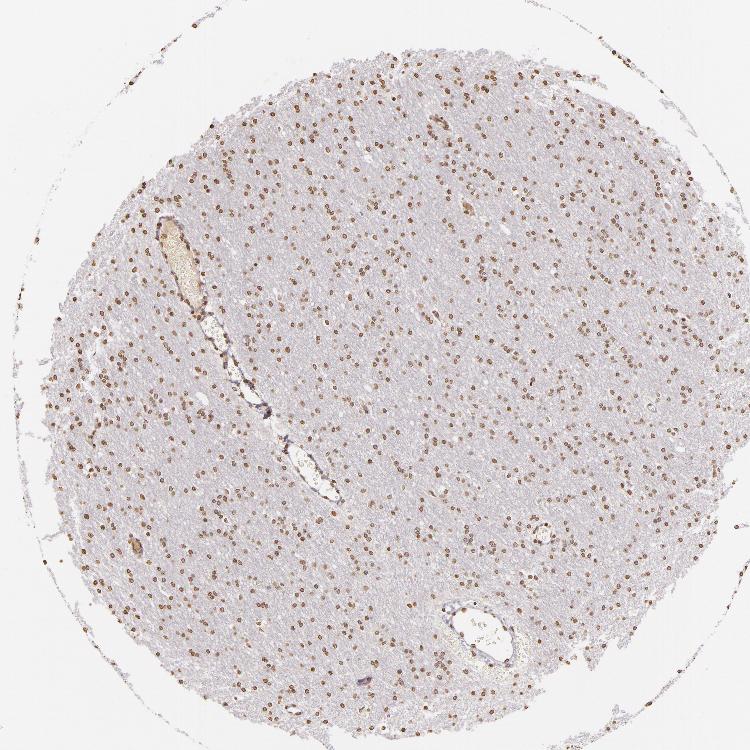

CEREBRAL CORTEX - Antibody stainingi

Antibody staining in the annotated cell types in the current human tissue is reported as not detected, low, medium, or high, based on conventional immunohistochemistry profiling in selected tissues. This score is based on the combination of the staining intensity and fraction of stained cells.

Each image is clickable and will lead to virtual microscopy that enables deeper exploration of all samples and also displays staining intensity scores, fraction scores and subcellular localization as well as patient and tissue information for each sample.

Antibody CAB002008Antibody CAB002009

Endothelial cells LowMedium

Glial cells LowMedium

Neuronal cells Not detectedMedium

Neuropil Not detectedNot detected